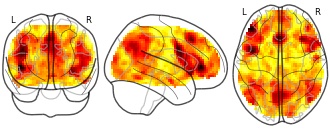

"name": "Multi_VBMgreater_fMRIenhanced",

"description": "Multi-modal analysis in BPD. Brain regions exhibiting greater gray matter and enhanced activation during emotion processing in BPD compared to healthy controls. Note: Results were thresholded at p<.0025. Note2: Results were updated (see Erratum for this publication).",